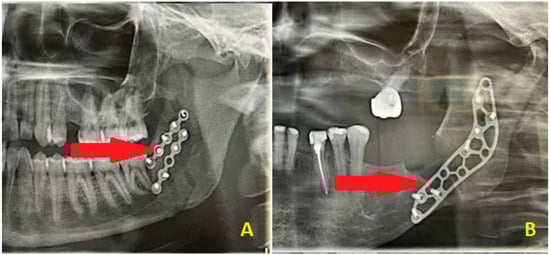

Figure 6. Other limitations of DPGs in assessing the postoperative mandible surgery results might be found in some cases of sagittal mandibular fractures, in which the plating position might not correlate with the fracture line patterns and might suggest an insufficient surgical result (A). The second situation (B) might be related to a combination of buccal cortical bone loss resulting from surgery on impacted wisdom teeth, which required PMP, while the fracture line can only be assessed intraoperatively and cannot be found on the postoperative radiograph. The red arrows point to the fracture line pattern, which is barely visible on the radiographs. In most cases, a routine DPG is not sufficient to fully evaluate each surgical outcome or assess the presence of a pure and well-defined fracture line; therefore, CT or low-dose CT is recommended. It is worth highlighting that DPG has many limitations. The use of PMP has been reported by a few authors so far, like Murakami et al. and Santos et al., because this approach is not common and strongly linked to individual patient cases, intraoperative features, and the scope of 3D bone loss estimation, which can be measured on CBCT but not on DPG [11,12]. The preventive and prophylactic measures to ensure good mandible bone stability, healing, and immobility are quite important. Other DPG limitations and weak points include only 2D visualization; poor visibility of cortical bone defects; ability to evaluate the position of the condylar head in the glenoid fossa, but not the head angulation; limitations in estimating bone fragment alignment and angulation after surgery; inability to fully assess sagittal fracture lines; inability to fully estimate proper bone alignment; good estimation of proper and symmetrical mandibular ramus height, but ramus slope and rotation not being visible; smaller bone fragments or secondary fractures not being visualized; the lingual cortical bone plate not being visible; non-displaced fractures or greenstick fracture lines being underestimated; and lack of correlation with intra-operative findings during surgery, which could falsely indicate misalignment and inadequate fracture reduction. It is also worth keeping in mind that computed tomography (CT and LDCT) must always be combined with a good patient anamnesis and careful surgical field assessment, sometimes followed by additional radiological studies or even endoscopy or USG to fully assess a typical trauma patient case [13]. On the other hand, where some mandibular surgery is scheduled, the usage of PMP is quite different, but its outcomes include bone stability, avoidance of future pathological fracture, and assurance of bone immobility to promote its adequate healing free of any local inflammation, granulation tissue formation, or other worrisome aspects. That is why CBCT has more to offer than an DPG: an improved fracture evaluation rate; 3D visualization; possibility of evaluation of both cortical and medullary bone; improvements in the condylar head position estimation in the glenoid fossa; a good method for evaluation of bone angulation and proper positioning; all fracture line patterns able to be clearly traced and evaluated; full postoperative bone alignment able to be investigated; improvements in the mandibular ramus evaluation in detail (bone structure, fragments angulation, rotation, height, and width); good visualization of all bone fragments along with the secondary fracture lines; improvements in the lingual cortical plate condition; reliable diagnosis of incomplete mandibular fractures; more improved diagnostics; and more accuracy when establishing the final bone reposition and bone alignment postoperatively. The limitations of panoramic radiographs in post-operative mandibular fracture reduction assessment (2D vs. 3D) should always be taken into consideration.